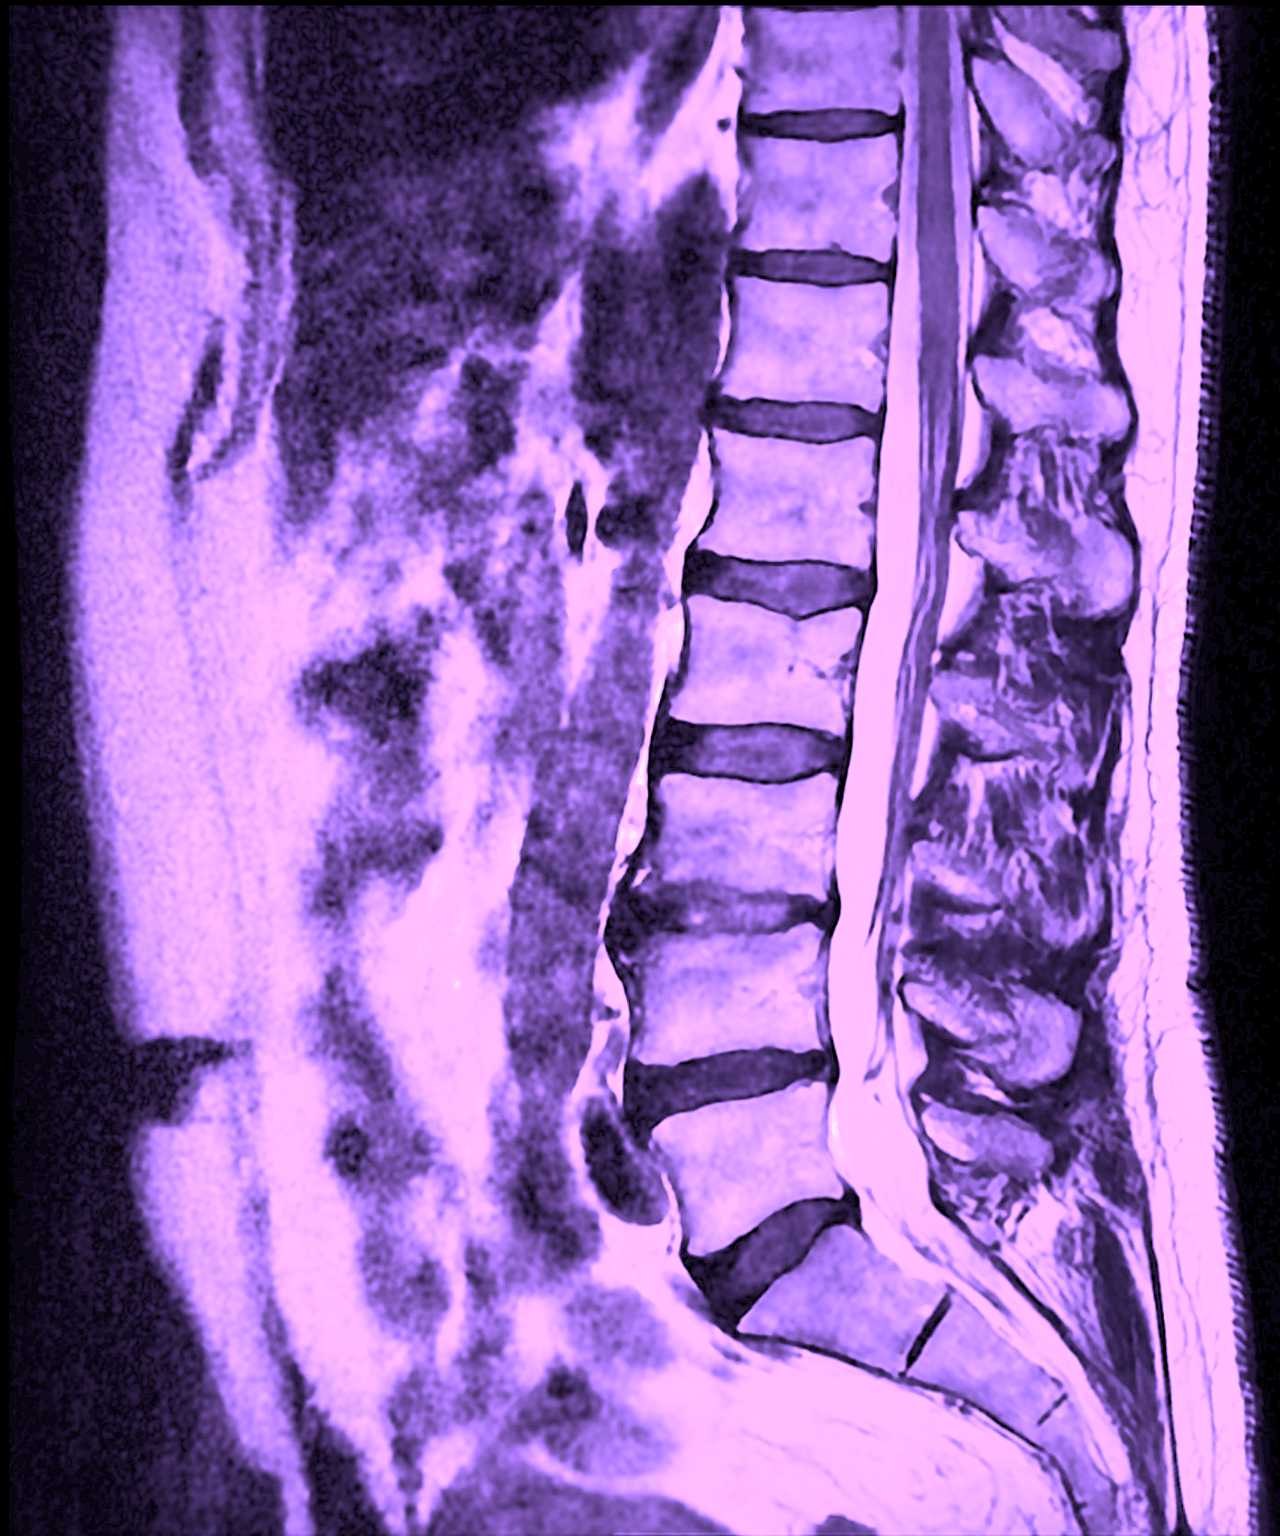

A MRI of the lumbar spine is an advanced, completely radiation-free method that provides very detailed images of the soft tissues of the spine. The scan uses a strong magnetic field and radio waves to image the discs, nerve roots, spinal canal, joints and surrounding soft tissue. Because the MRI is particularly good at showing soft tissue, the examination is often used to assess whether back pain is due to nerve damage, disc changes or other structural causes that are not visible on a regular X-ray.

An MRI examination of the lumbar spine is mainly used to map structural changes that can explain pain or neurological symptoms. Common findings include herniated discs, which means that part of the disc's soft core bulges out. This can, but does not necessarily, result in pressure on a nerve root. The examination also shows narrowing of the spinal canal (spinal stenosis) as well as show age-related changes in discs and joints, such as disc degeneration or osteoarthritis in the facet joints. In some cases, MRI can also reveal inflammation, infection, fractures, tumors or other rarer conditions that require further investigation or treatment.